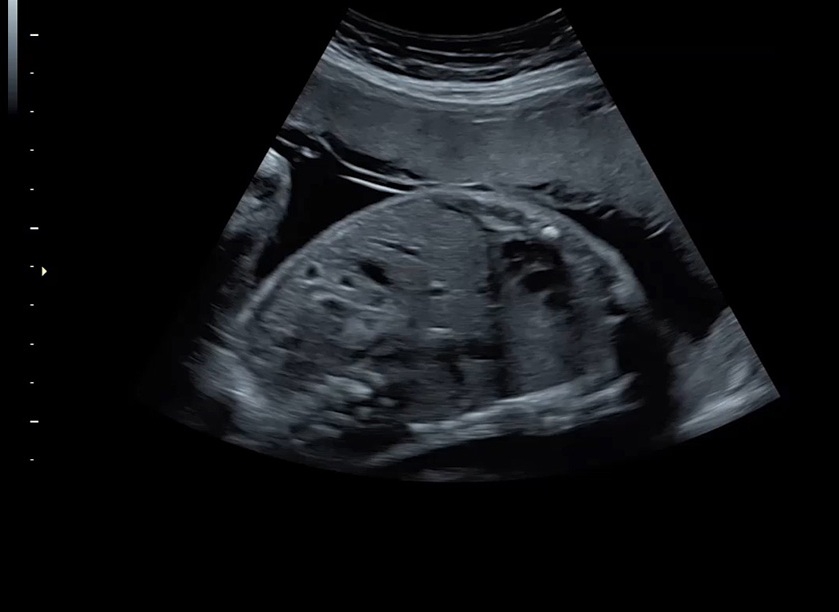

• Высокое качество изображений: Voluson S8 обеспечивает высококачественные изображения, позволяющие детально оценить состояние плода и обнаружить возможные патологии.

• Сложные инструменты для оценки качества плода: Сканер оснащен инновационными инструментами, позволяющими проводить детальную оценку состояния плода, включая его сердечную деятельность, анатомию и кровоток.

• Высокочувствительные датчики: Ультразвуковой сканер Voluson S8 оснащен высокочувствительными датчиками, что позволяет проводить полноценное обследование даже у пациентов с сложными анатомическими особенностями.